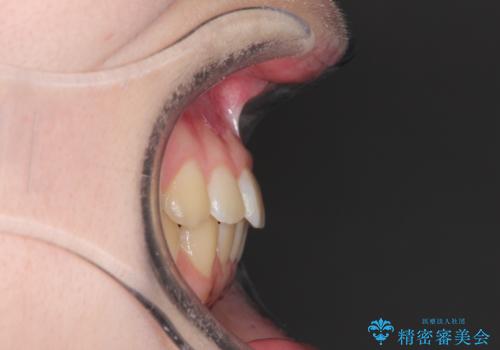

なるべく通院回数を減らして矯正したい インビザラインでのガタガタ矯正

- 上下の歯並びを治したいとのことで来院されました。

受験生ということもあり、なるべく通院回数を減らしての矯正を希望されたので、インビザラインで治療をすることにしました。